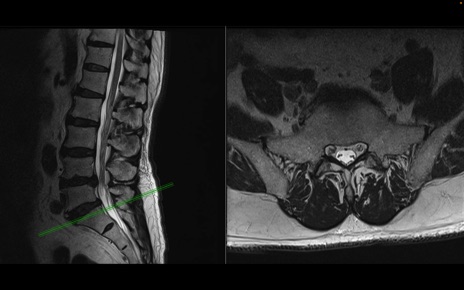

【整形】TIPS症例2 腰椎MRI 横断像と矢状断像

【症例】70歳代男性

【主訴】左下肢痛

【現病歴】2週間前くらいから腰痛、左下肢痛あり。左臀部から大腿、下腿外側のしびれが常時ある。歩行とともに同部位の痛みあり。

【身体所見】Lasegue70-/60+、Bragard-/±、PTR ±/±、ATR -/-、IP 5/5、TA 5/4、TS 5/5、EHL 右第1足趾なし/3、FHL 5/5、hypersthesia(-)、足背動脈触知良好

異常所見と診断は?